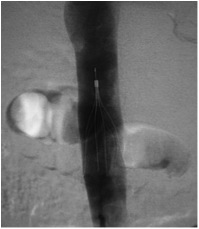

Consiste no implante de um dispositivo metálico na veia cava (veia que drena o sangue do corpo para o coração) com o objetivo de “filtrar” o sangue e “capturar” possíveis coágulos que possam se desprender da veia acometida pela trombose.

É realizada com anestesia local através da punção da veia femoral (na virilha) ou jugular (pescoço).